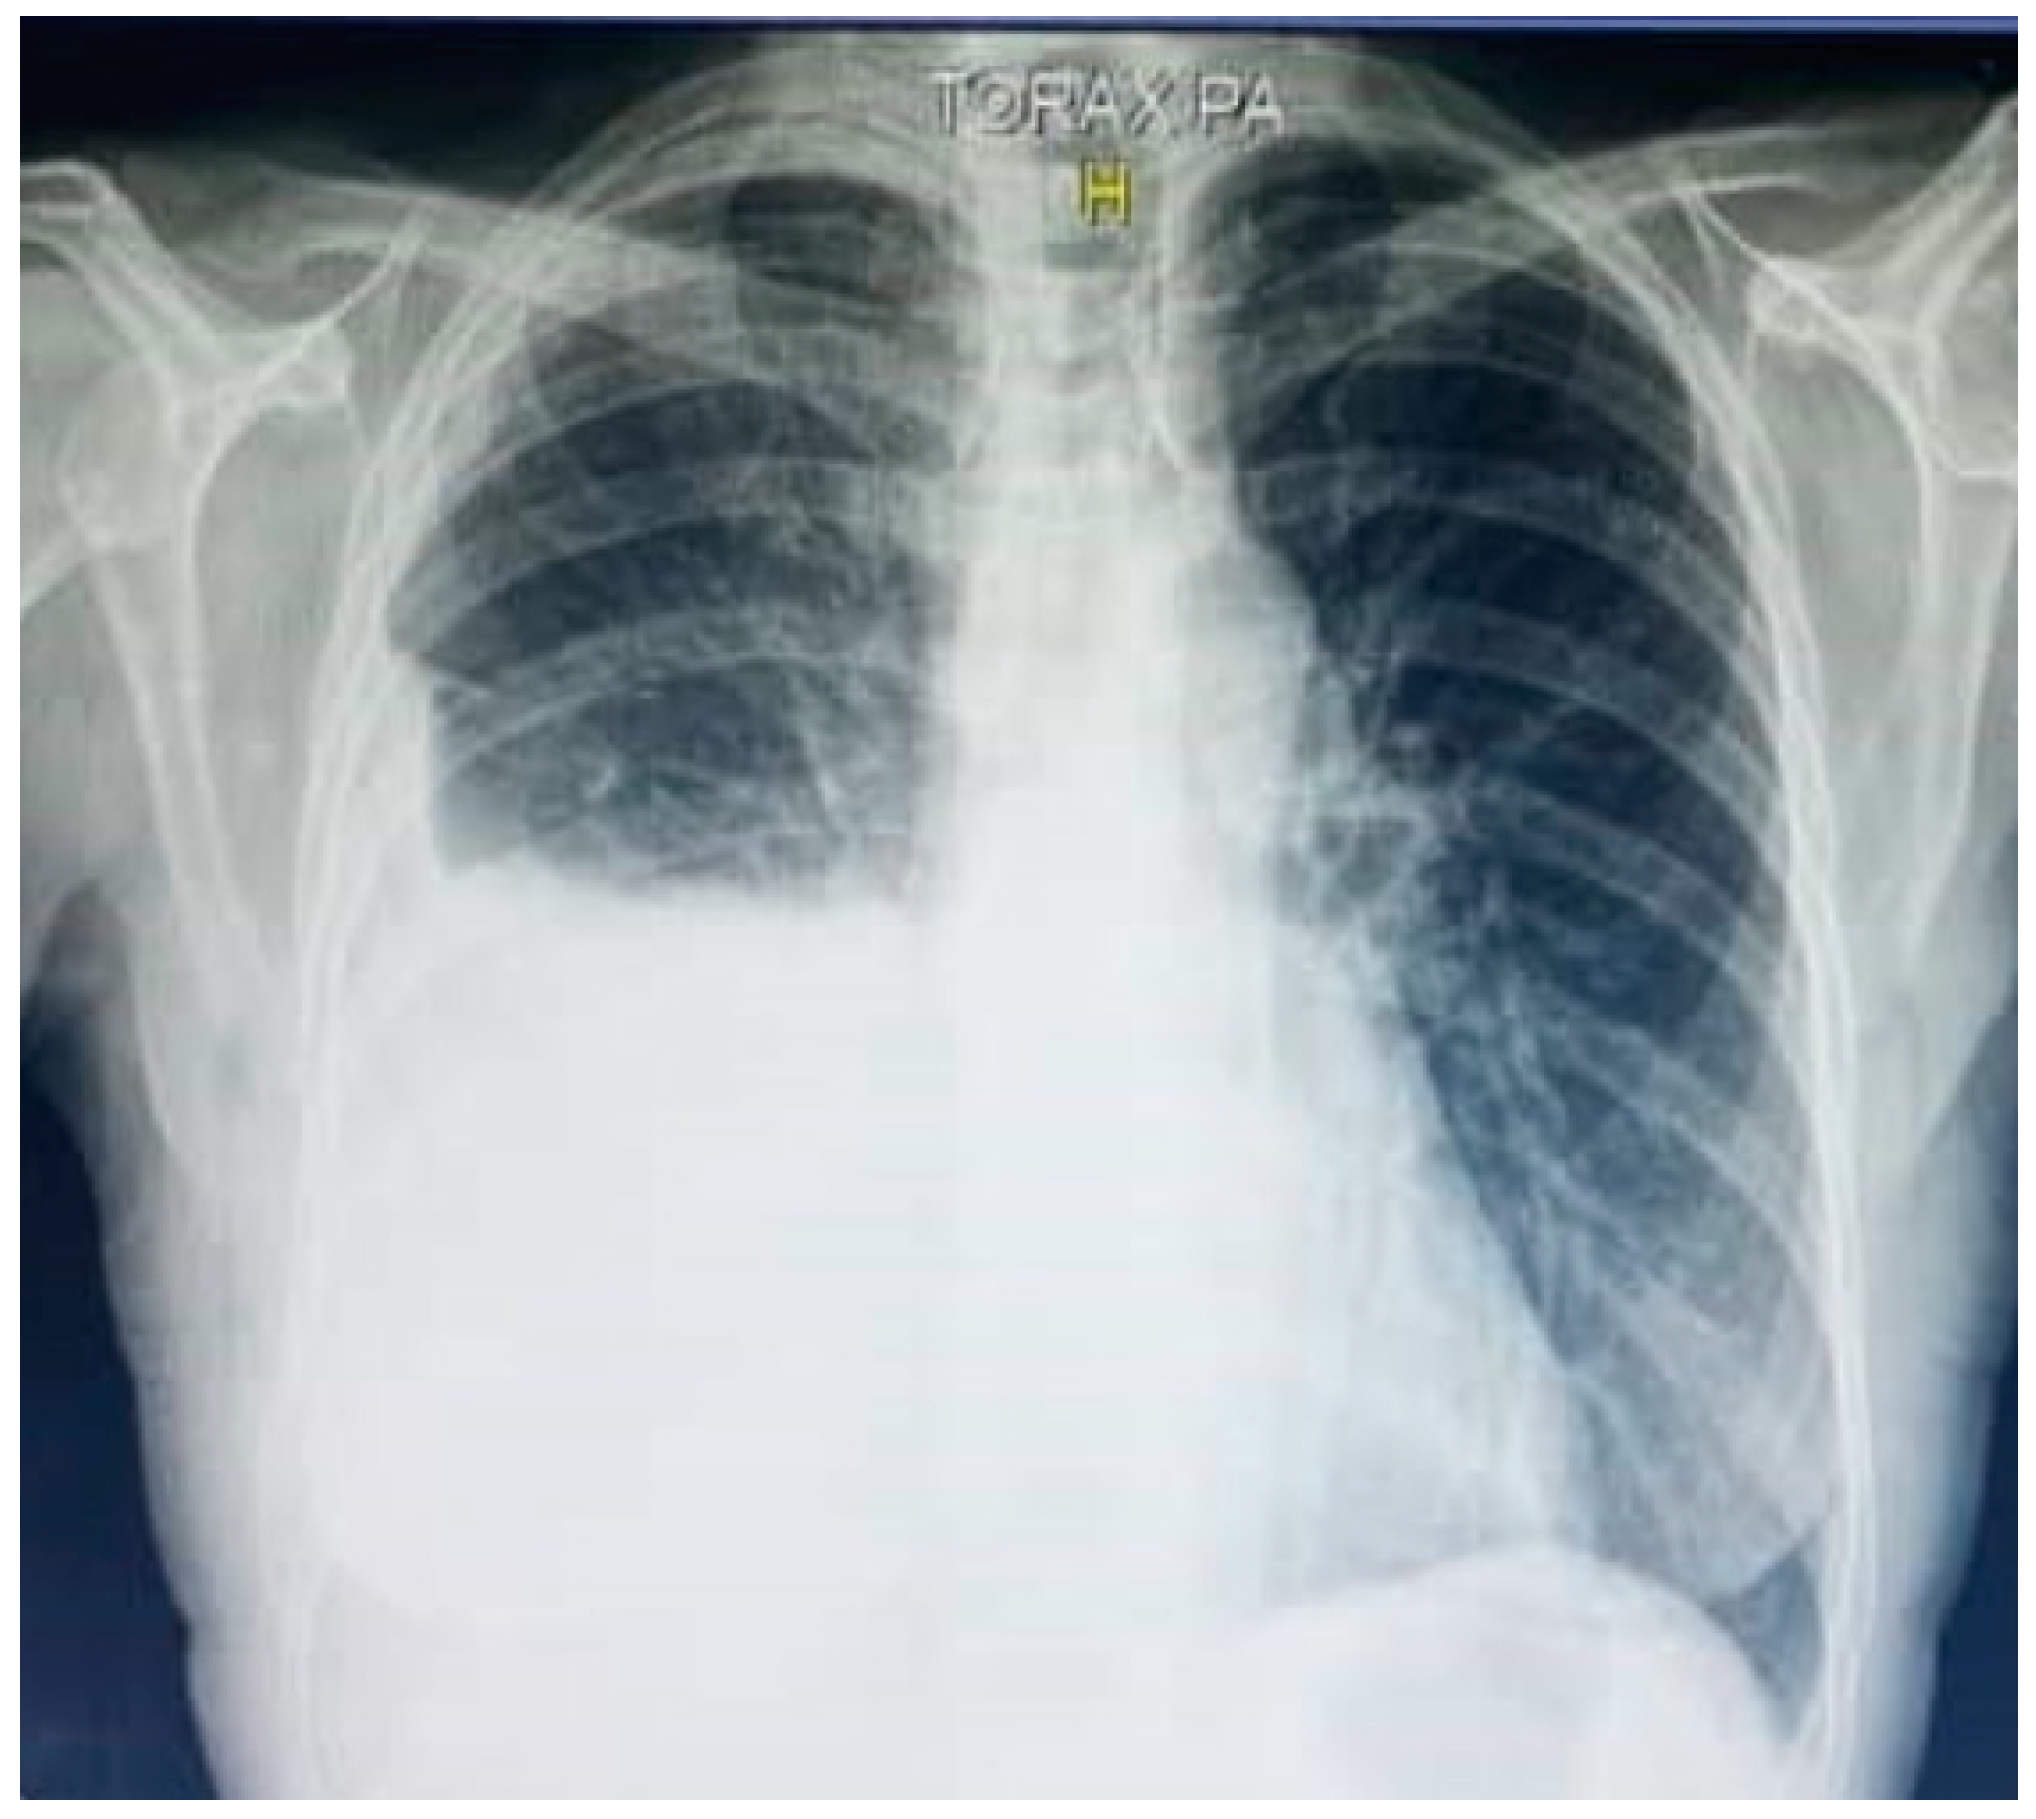

2.1. Diagnostic Imaging and Video-Assisted Thoracoscopic Surgery (VATS)